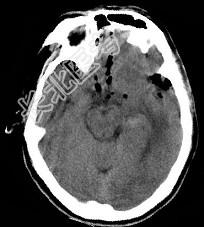

- 单项选择题男,32岁, 外伤后一天,CT检查如图, 下面何项诊断最恰当 ( )

A、脑出血

B、颅脑外伤

C、颅内积气

D、脑膜瘤

E、脑出血并颅内积气